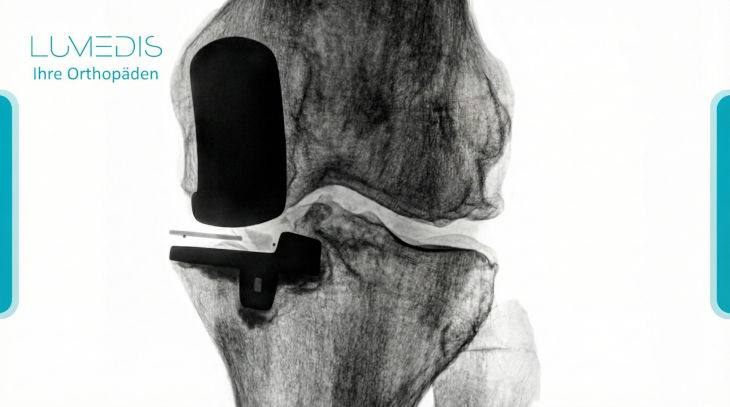

Die Anfertigung eines Röntgenbildes spielt zu verschiedenen Zeitpunkten beim Einbringen einer Knieprothese eine Rolle.

- Es ist wichtig, dass vor der Implantation der Knieprothese im Röntgenbild das Ausmaß der Gelenkschädigung dargestellt und beurteilt werden kann.

Weiterhin ist ein Röntgenbild für eine operative Vorplanung zwingend notwendig, um die Achskorrekturen und Größen der Prothesenkomponenten im Vorfeld zu bestimmen.

- Nach der Operation sollte ebenfalls eine Kontrolle der Positionierung der einzelnen Anteile der Prothese mittels Röntgenbild erfolgen.

- Kommt es zudem zu starken Beschwerden im Verlauf oder Hinweisen auf eine Prothesenlockerung kann dies ebenfalls im Röntgenbild beurteilt werden.

Nach einer Prothesenimplantation ist nach der radiologischen Erstkontrolle kein weiteres Röntgenbild nötig.

Bei Beschwerdefreiheit sollte alle 5 Jahre ein Röntgenbild gemacht werden, damit einer Frühlockerung entgegengewirkt werden kann.